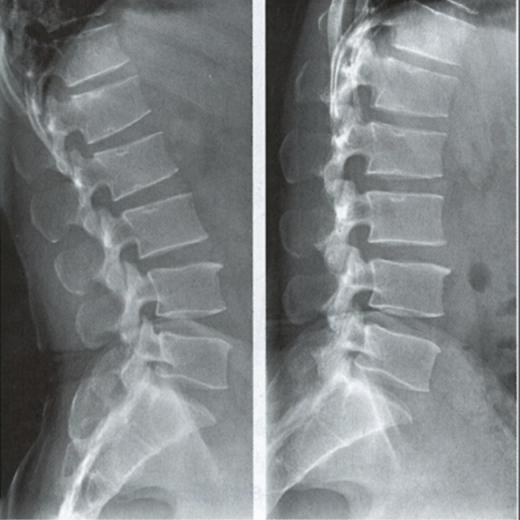

能屈能伸的腰椎——腰椎動(dòng)力位

腰椎動(dòng)力位,也稱為過(guò)屈過(guò)伸位,可以理解為兩個(gè)極限體位下的側(cè)位片,腰椎動(dòng)力位通過(guò)做最大程度彎腰(過(guò)屈)和后仰(過(guò)伸)的動(dòng)作拍攝側(cè)位片,來(lái)觀察腰椎在極限活動(dòng)下的表現(xiàn)。如果說(shuō)腰椎側(cè)位片能靜態(tài)體現(xiàn)椎體的解剖學(xué)結(jié)構(gòu)、序列及生理曲度改變,那么腰椎動(dòng)力位則是評(píng)估腰椎動(dòng)態(tài)功能性的檢查。

腰椎過(guò)伸位:是指腰部盡可能向后伸展,以雙髖關(guān)節(jié)位支撐點(diǎn),運(yùn)動(dòng)前后骨盆位置無(wú)改變。腰椎過(guò)伸時(shí),向前的曲度大于生理曲度,上部向后傾斜。

腰椎過(guò)屈位:是指腰部盡可能向前彎曲,以雙側(cè)髖關(guān)節(jié)位支撐點(diǎn),運(yùn)動(dòng)前后骨盆位置無(wú)改變。腰椎過(guò)屈的表現(xiàn)位向前的曲度減小、變直,上部向前傾斜。

當(dāng)1度及以上的滑脫時(shí)才可以在普通腰椎側(cè)位上觀察到,而1度以下的滑脫或失穩(wěn)則在普通側(cè)位片上難以發(fā)現(xiàn),這時(shí)候就需要借助腰椎動(dòng)力位進(jìn)行診斷。

腰椎動(dòng)力位 左圖為過(guò)伸位、右圖為過(guò)屈位